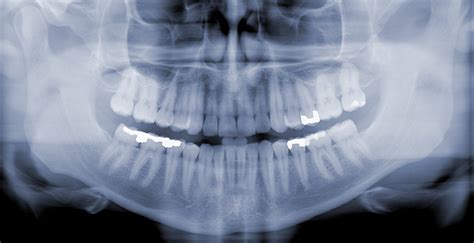

Pokiaľ máte podozrenie, že psík či mačka pozrel cudzí predmet, volajte radšej veterinári. Veľa závisí od druhu predmetu - či je malý, veľký, ostrý alebo tupý az akého je materiálu. U týchto predmetov sa zvracanie rozhodne neodporúča z dôvodu, že by napríklad ostrý predmet poranil sliznicu a mäkké okolité tkanivá žalúdka a pažeráka, čo nie je rozhodne žiaduce. Dalo by sa povedať, že všetky, ale najhoršie sú však dlhé nite a povrázky, rôzne druhy textílií (ponožky, handry, uteráky, utierky). Tie sa čoskoro menia na tzv. lineárne cudzie teleso, ktoré je veľmi nebezpečné, pretože sa dlhé časti zamotávajú do črevnej peristaltiky, čím môže vzniknúť tzv. Lineárne cudzie teleso svojim proximálnym koncom môže zostať zakotvené napr. v pažeráku (napr. rybársky háčik s vlascom, ihla s niťou, a ďalšie) a distálnym koncom pokračuje ďalej do žalúdka či čriev. Pozor najmä na tzv. Pokiaľ prídete do ordinácie s podozrením, pravdepodobne veterinár ihneď urobí RTG snímku, niekedy využije možnosti kontrastných látok, ktoré krásne zobrazujú priechodnosť tráviaceho traktu. Cizí těleso v žaludku psaKaždé cizí těleso v žaludku psa může mít jiný průběh. V nejlepším případě pes těleso po určitém čase vyzvrací. Větší těleso se bohužel zpět do jícnu už nevrátí a zůstane v žaludku. Po delší době nevolností a zvracení se dostává dále do střev. Cizí těleso v žaludku je charakteristické žízní, zvracením a ztrátou chuti. Cizí těleso ve střevě psaStřeva jsou nejdelší a také nejtenčí úsek trávicího traktu. Právě proto nejvíce cizích těles končí právě ve střevech. Pokud je cizí těleso příliš velké hrozí, že se střevo ucpe. To značí vážný problém, který vyžaduje veterinární pomoc. Bez rychlé pomoci může střevo i prasknout. Přítomnost cizích těles ve střevech psa se projevuje zvracením, vodnatou stolicí s příměsí krve, bolestí břicha, neklidem a méně často zácpou. Nejzávažnější komplikace umí vytvořit tzv. lineární cizí těleso. Může jít například o nit, podlouhlou textílii, igelitové sáčky, či jiné předměty, které jsou dlouhé, mohou způsobit obstrukci na dvou a více místech a navíc tedy nařasení střev, která se kolem nich postupně stáhnou.